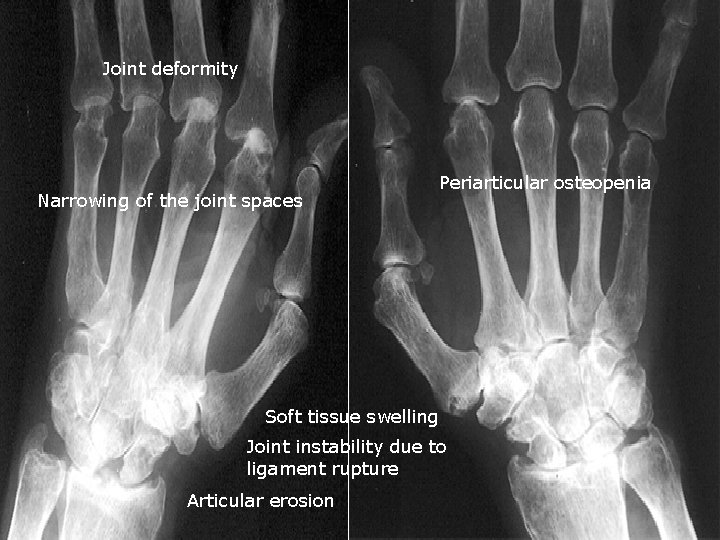

Rheumatoid arthritis :

Joint deformity Narrowing of the joint spaces Periarticular osteopenia Soft tissue swelling Joint instability due to ligament rupture Articular erosion